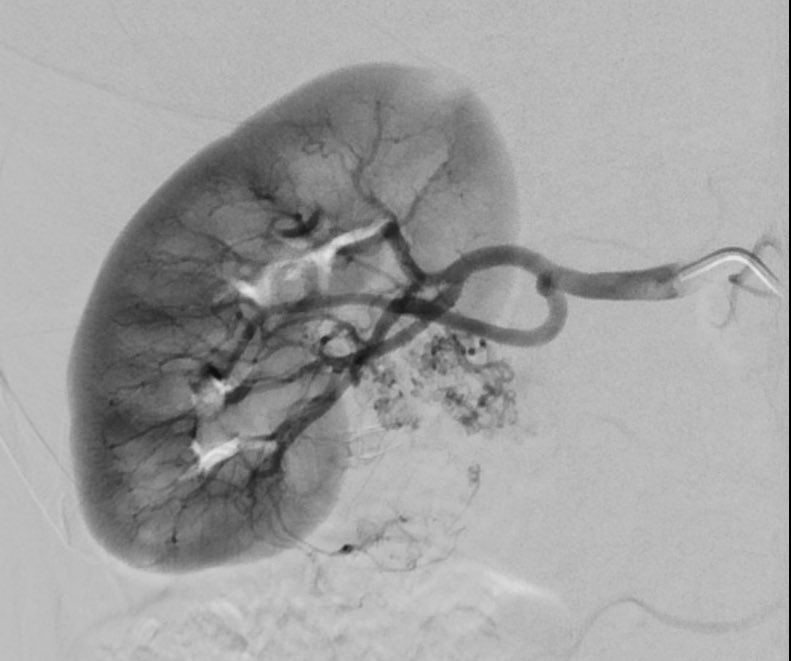

David Léon MD@IdCathThat·

A renal angiomyolipoma (AML) requiring treatment because high bleeding risk (figure 1). Angiogram shows the "sunburst" appearance of the mass (figure 2). After treatment with 100% alcohol and lipiodol the mass is completely devascularized (figure 3).

David Léon MD tweet mediaDavid Léon MD tweet mediaDavid Léon MD tweet media

English